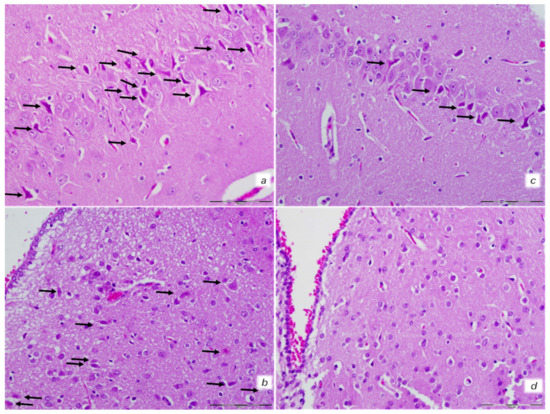

2.8.2. Brain Histology

2.8.3. Lung Histology